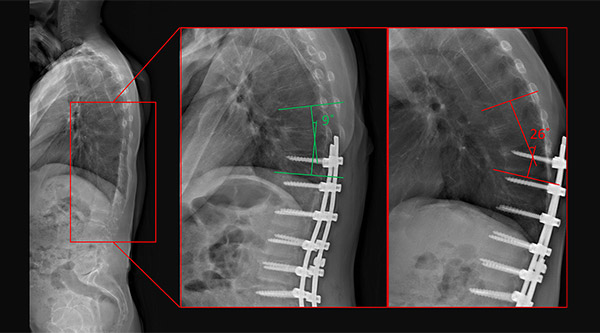

Radiology images of a patient with PJK. (Left) baseline (no hardware), (middle) immediate postoperative image (no PJK), and (right) 2.5 years follow-up image (PJK)